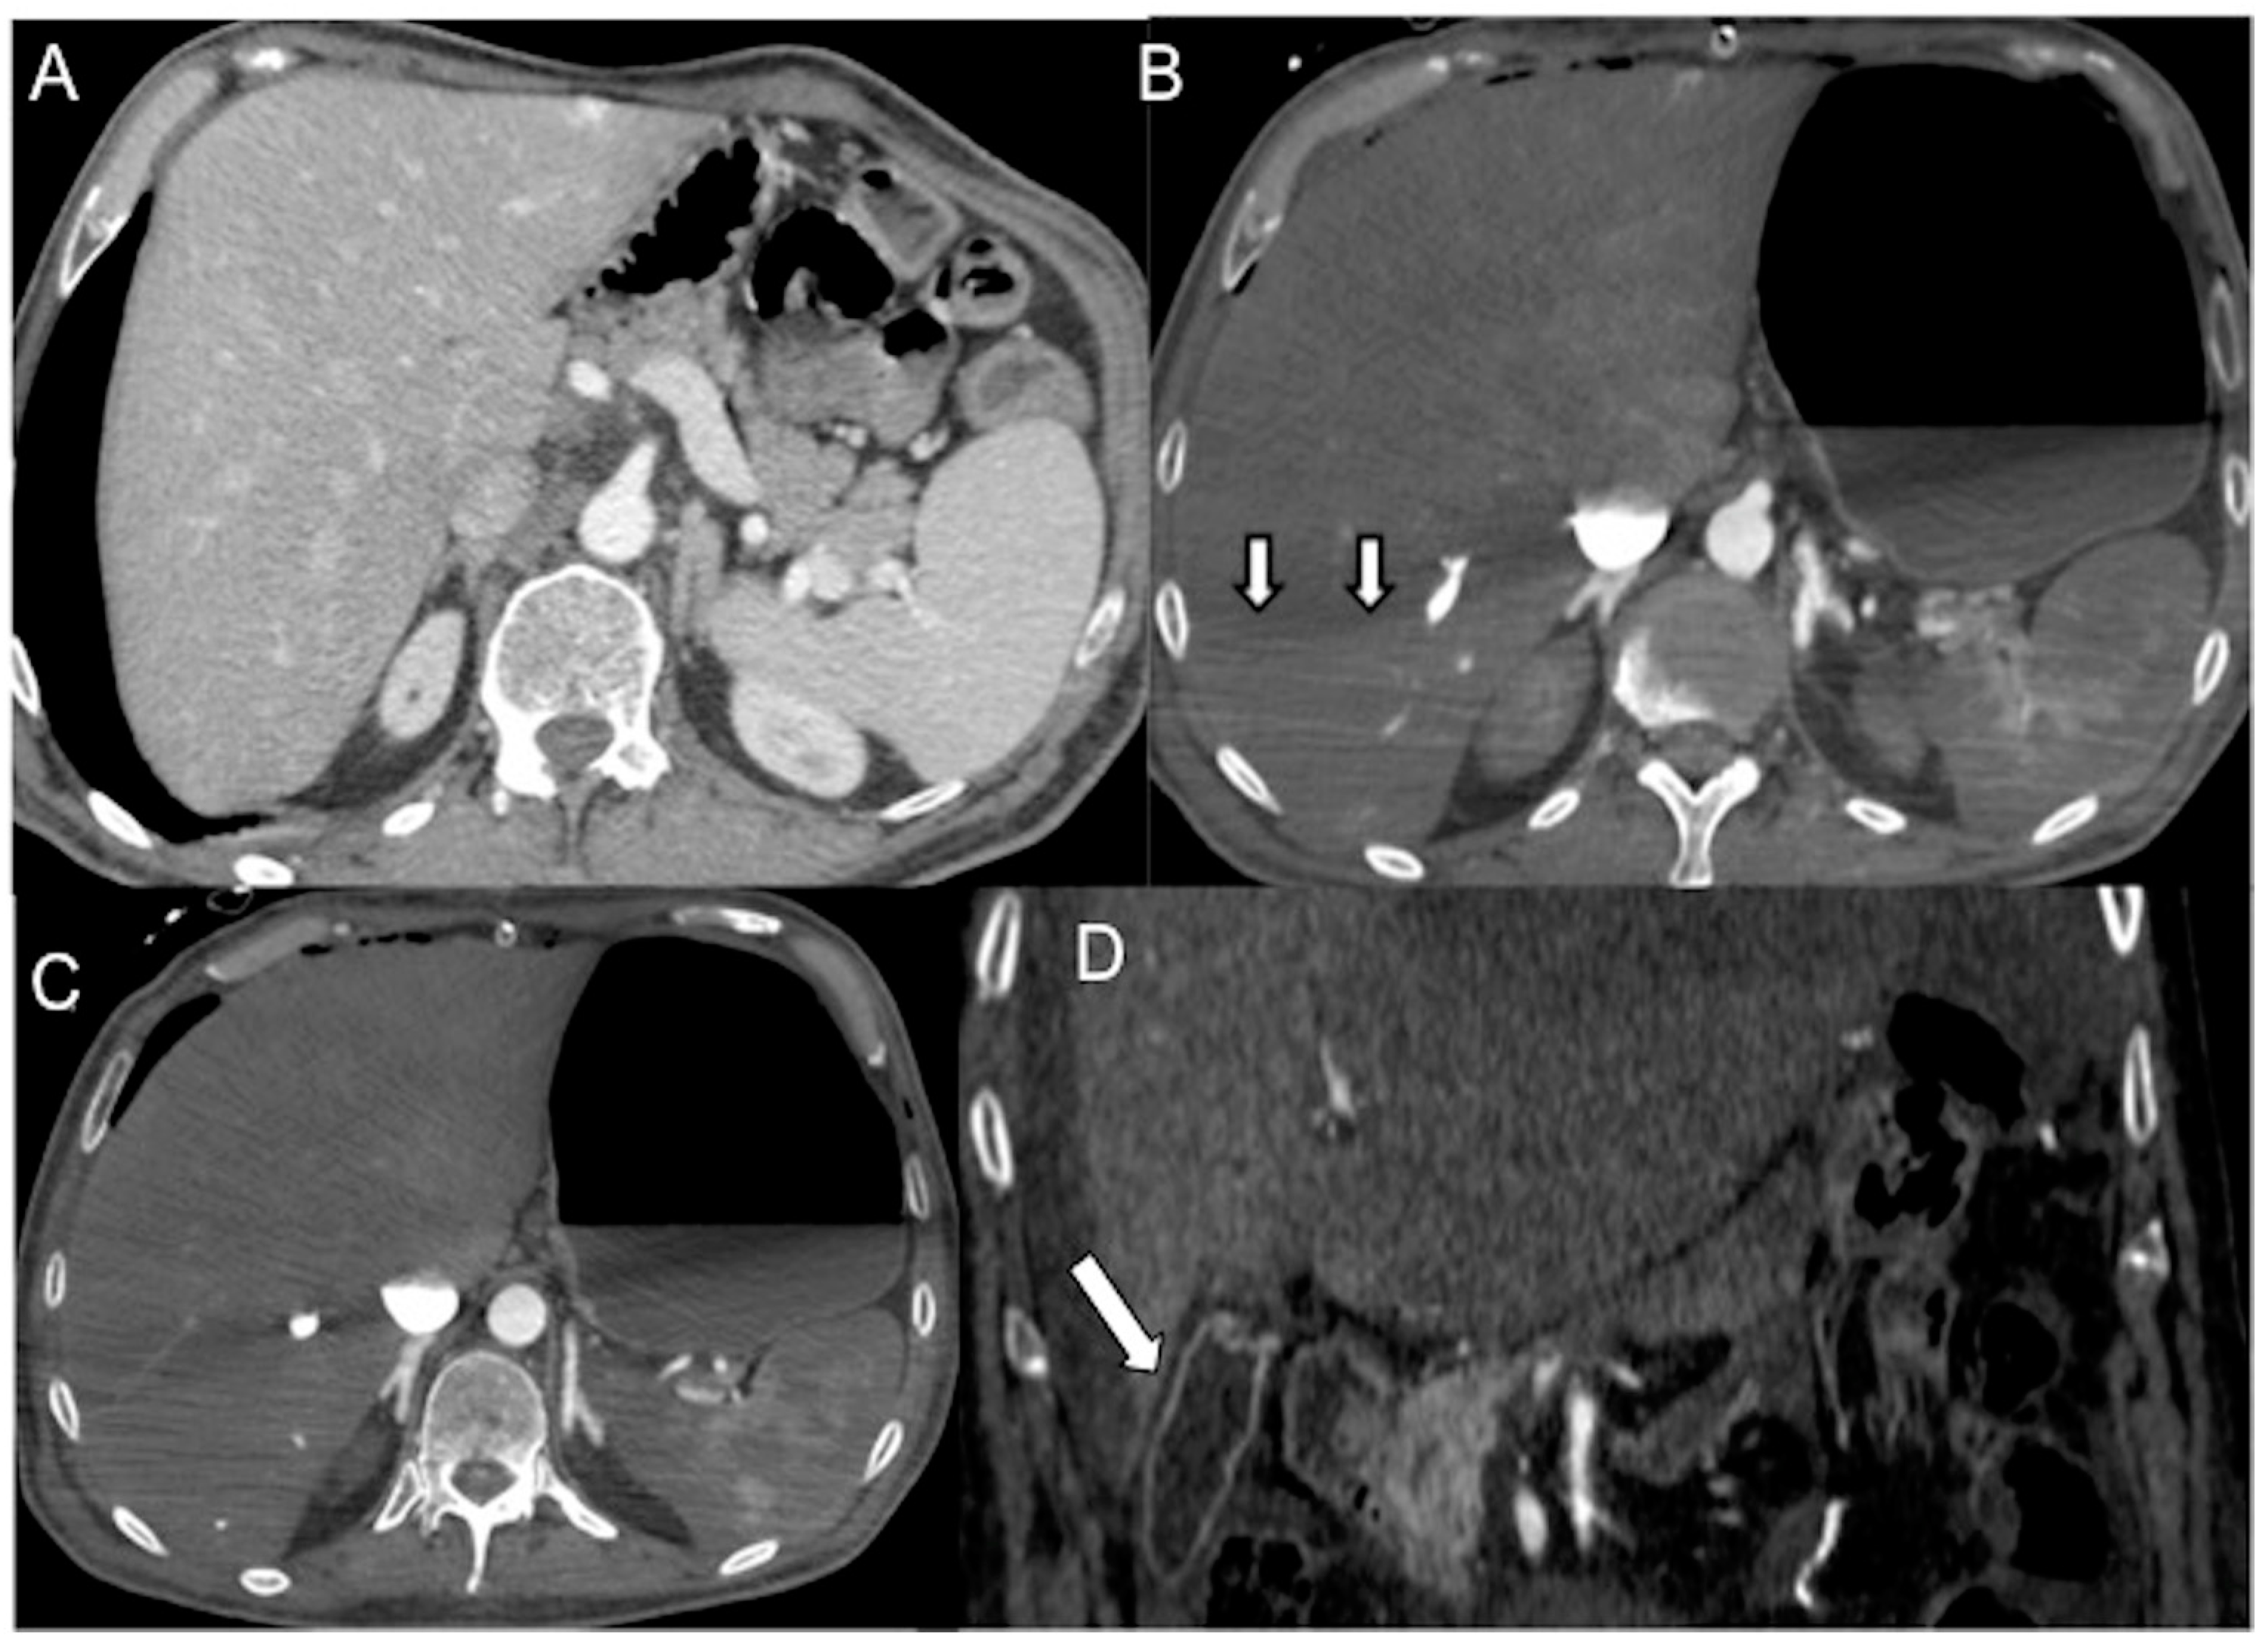

- In irreversible end-organ dysfunction, injected IV CM circulation is supported only by the pressure applied by the automated power injector and the density of contrast material. Circulatory arrest leads to dense contrast pooling and layering in the SVC, IVC (inferior vena cava), and right heart chambers with non-opacified left heart chambers or arterial vessels (Figure 1) [43,45,49,50,51,52]. This may be called the “non-beating heart” pattern. Cardio-pulmonary aggressive resuscitation must immediately be initiated within the framework of a predetermined emergency plan.

Figure 1. Non-beating heart in a 72-year-old man with sudden-onset severe dyspnea/shock and asystole during thoraco-abdominal CT. (A) CECT axial image shows dense contrast in the round superior vena cava, and reflux in the azygous arch; (B) contrast pooling and layering in the right atrium and IVC with retrograde opacification of coronary sinus (arrow). (C) CM fills the round inferior vena cava with hypostatic reflux into the hepatic veins, hemiazygos vein, partially splenic vein, and (D) right renal vein. Note no mixing of blood with CM and no opacification of the pulmonary arteries, aorta, and left cardiac chambers, suggestive of a non-beating heart. Prompt initiation of cardio-pulmonary resuscitation to restore circulation was useless. Autopsy: ruptured myocardial infarction.